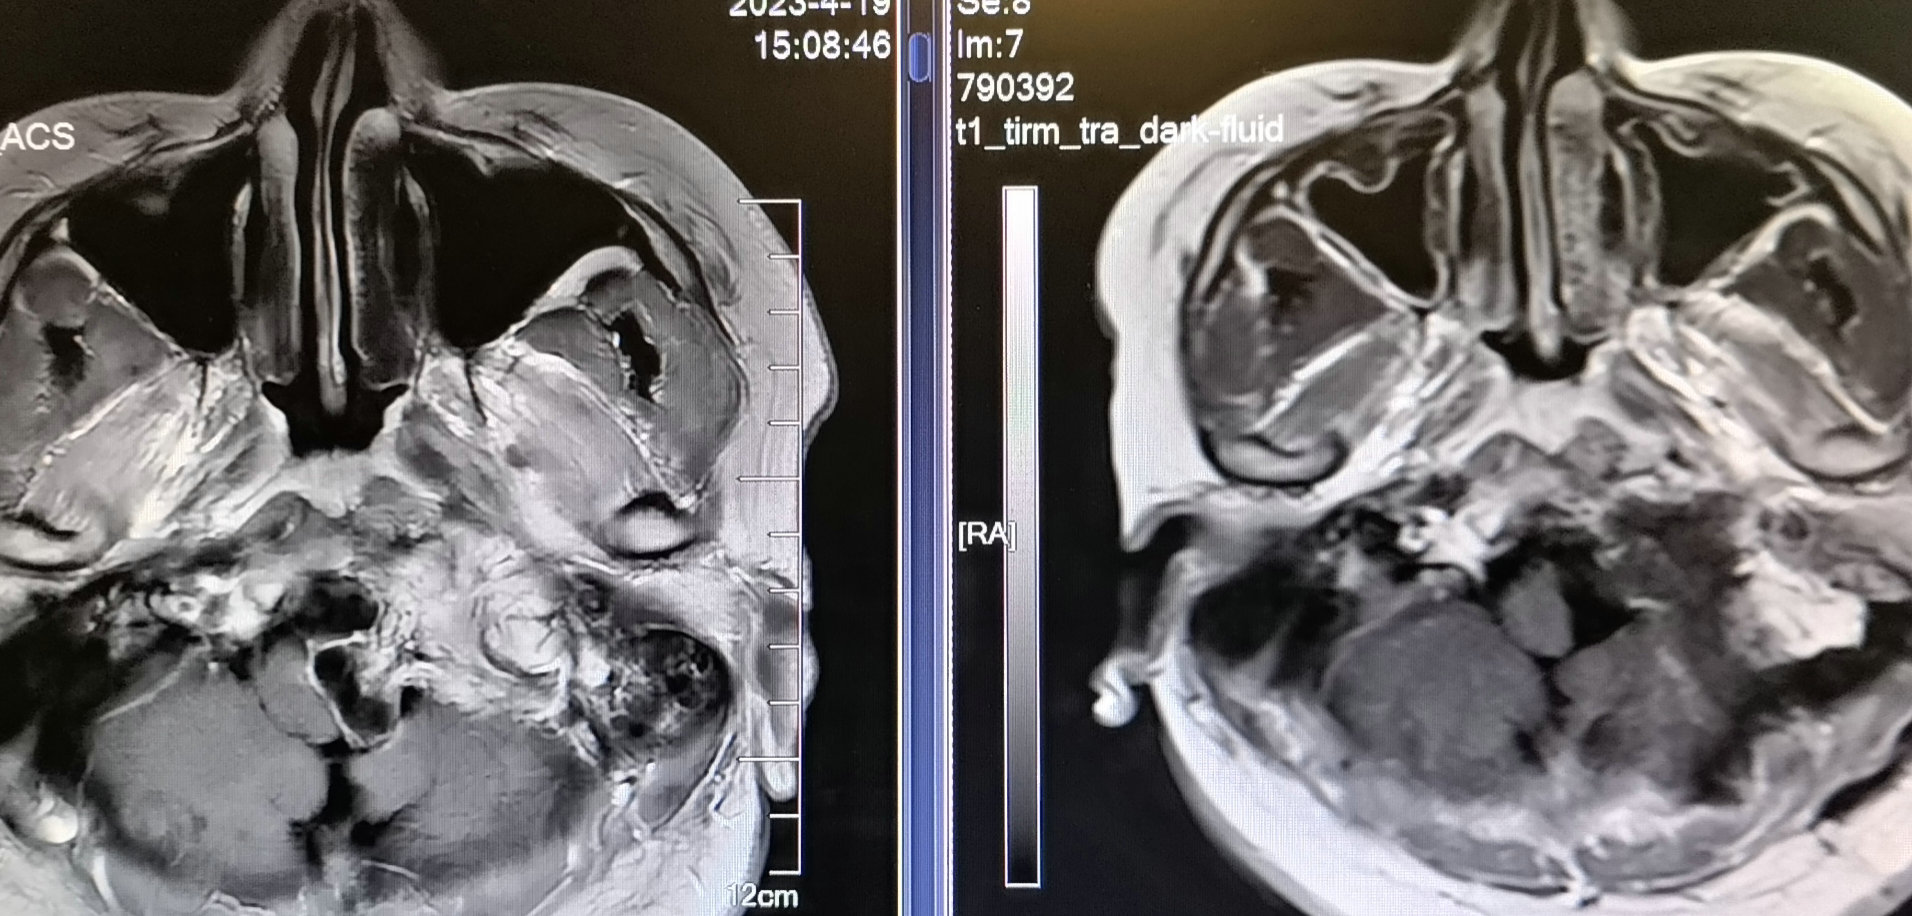

术前磁共振